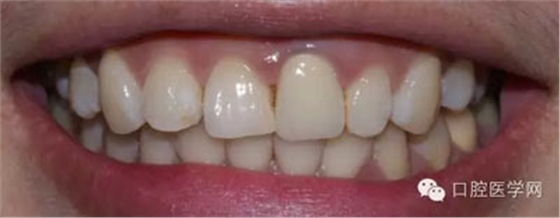

術(shù)前照